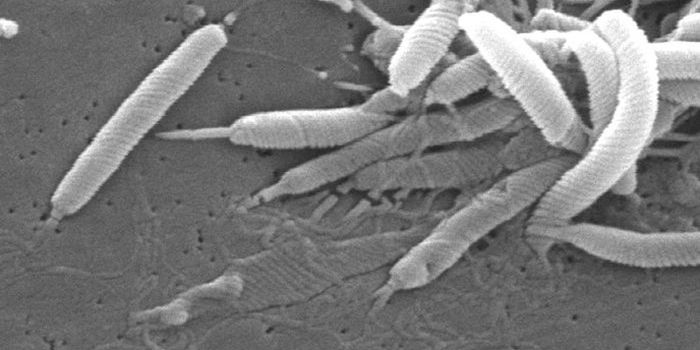

MAY 05, 2019MicrobiologyHelicobacter pylori doesn't only withstand the harsh stomach environment, it can thrive there, sometimes causing ulcers ...